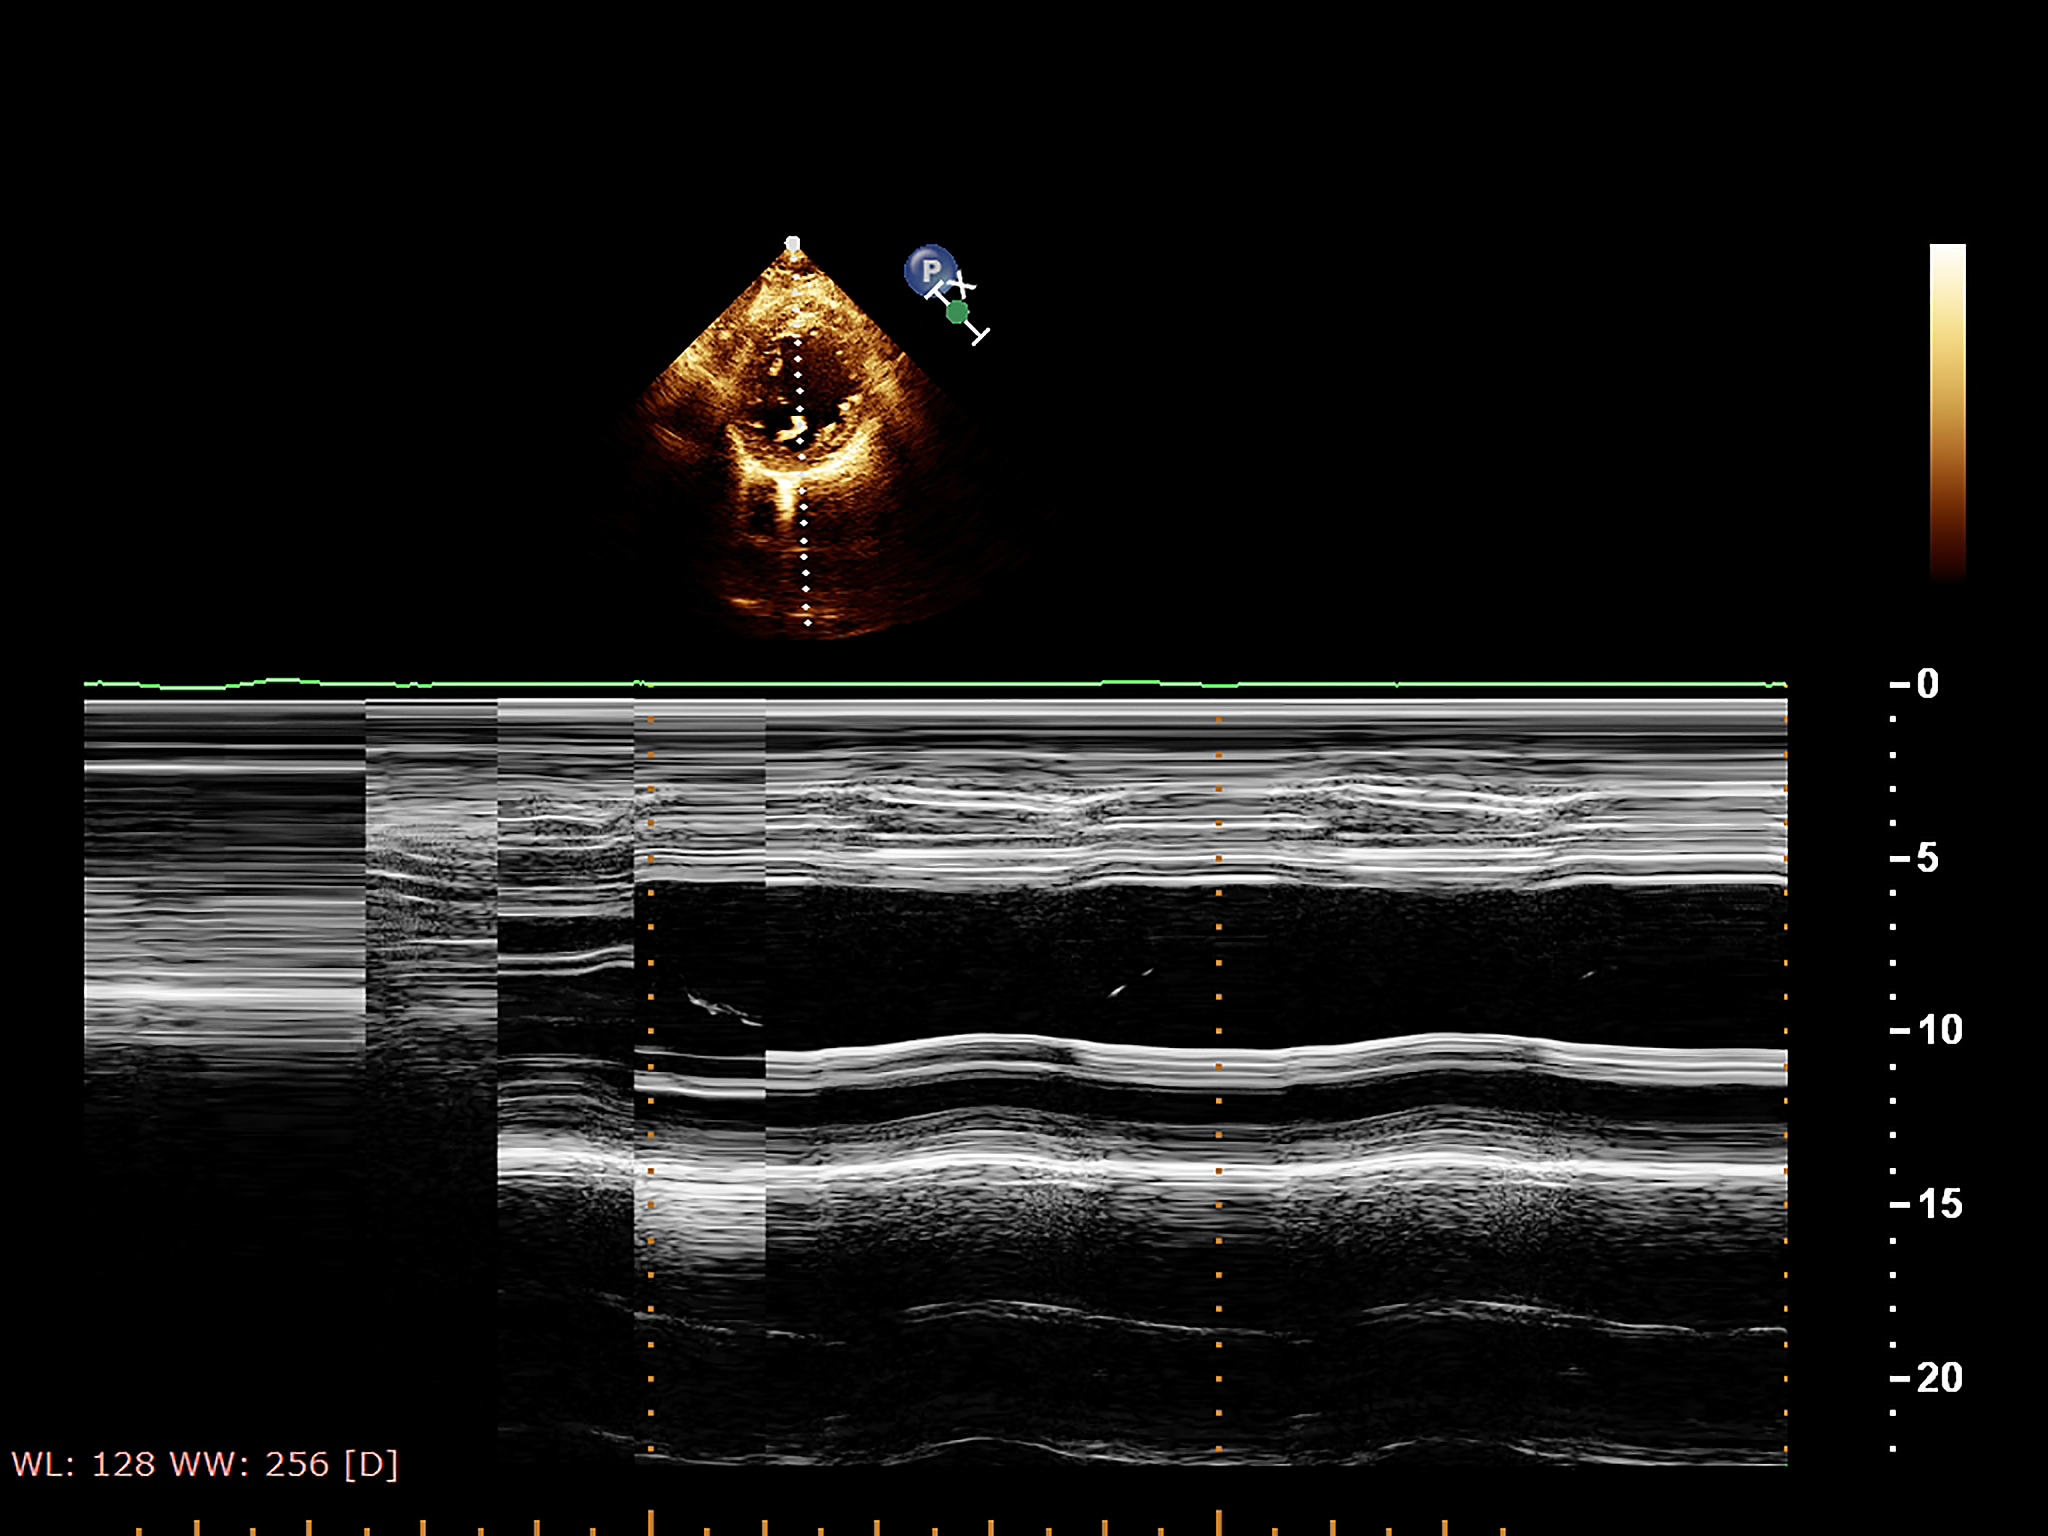

超声造影是诊断颈动脉斑块破裂合并漂浮血栓形成的重要手段。在超声造影图像中,我们可以观察到颈动脉斑块破裂的特征,例如斑块边缘不规则、斑块内有空洞等。此外,我们还可以看到漂浮血栓在颈动脉血管中移动的图像。